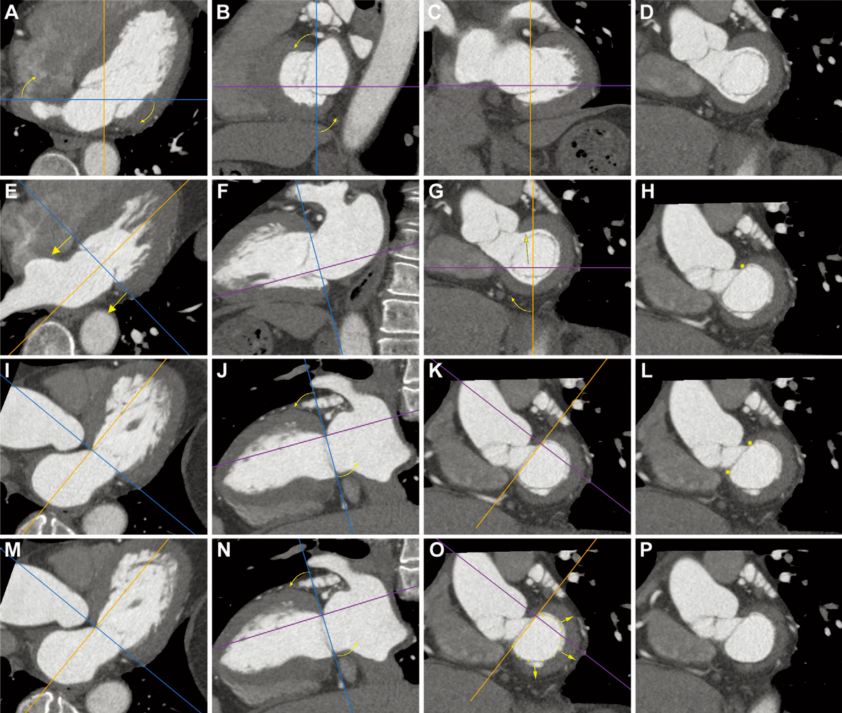

随着适应证的扩大,二叶瓣主动脉瓣(BAV)在TAVR患者中的比例预计会增加;然而,没有研究调查这些患者未来再行TAVR的冠状动脉阻塞风险。由四川大学华西医院陈飞教授汇报的本研究旨在探究BAV和三叶瓣主动脉瓣膜(TAV)的主动脉瓣狭窄患者相比,在先前植入的自膨瓣情形下,再行经导管主动脉瓣置换术(TAVR)冠脉阻塞的风险。

在2014年1月至2019年12月期间,对86例0型BAV、70例1型BAV和132例TAV患者进行了计算机断层扫描(CT)模拟分析,定义冠脉阻塞风险,所有患者均接受了1个Venus-A瓣膜的TAVR(Venus Medtech)。

结果显示,分别有36.1%和27.8%的患者出现了再次TAVR时CT得出的左冠状动脉口(LCO)和右冠状动脉开口(RCO)阻塞风险。然而,0型BAV组的发病率明显低于1型BAV或TAV组LCO:OR:1.00[参考值] vs OR:2.49;95%CI:1.24-5.01 vs OR:2.60;95%CI:1.40-4.81;RCO:OR:0.00[参考] vs OR:2.14;95%CI:1.02-4.48 vs OR:1.97;95%Cl:1.02-3.80)在再次TAVR期间,61.5%的阻塞高危LCO和58.8%的阻塞高危RCO的瓣叶撕裂技术可能无法改善冠脉流量。0型BAV组的百分比统计学上显著或数值上低于其他组(LCO组:26.3% vs 62.1% vs 73.2%;总体P=0.001;RCO组:43.8% vs 65.2% vs 61.0%;总体P=0.374)。

研究指出,解剖特征的差异可能影响未来再次TAVR的可行性。0型BAV解剖结构与再次TAVR期间CT确定的冠状动脉阻塞风险的发生率低相关,瓣叶撕裂技术在这些人群里面可能更可行。